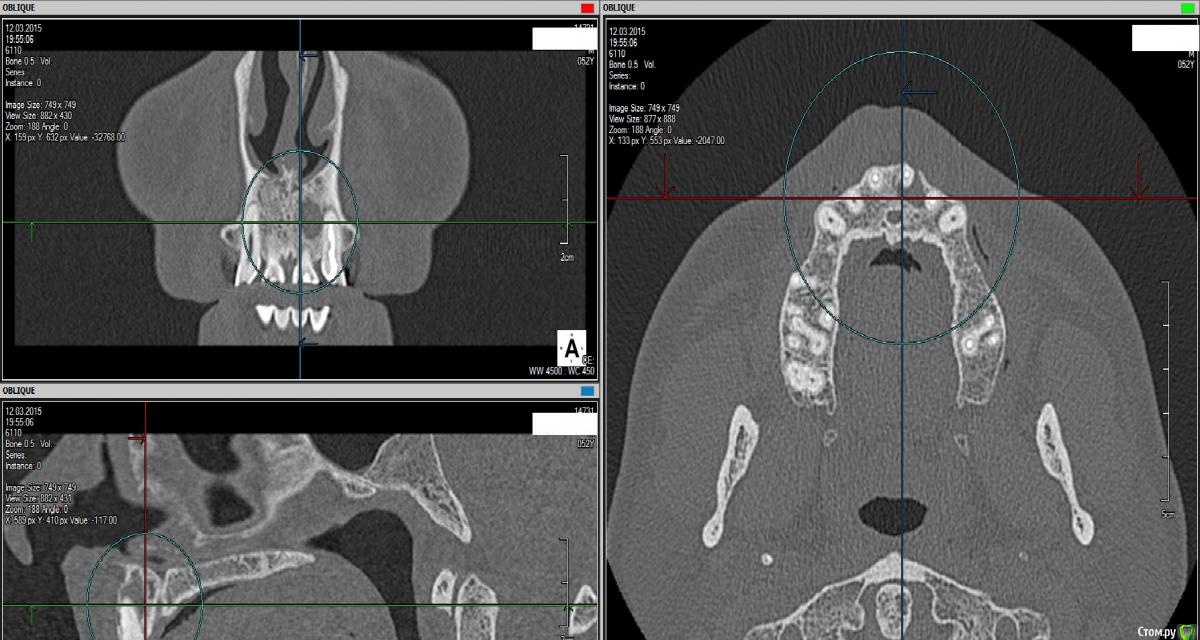

Нагаре Опубликовано 23 марта, 2015 Поделиться Опубликовано 23 марта, 2015 Здравствуйте.Поставили диагноз - киста 21 зуба. Судя по всему давнишняя. Ходил на консультации. Половина (хирурги) говорят удалять зуб, резекцию делать поздно и чтоб не слушал никого. Другая половина (терапевты) говорят что можно полечить, но без гарантий, процент успеха называют от 50 до 70%. Решил тут спросить совета - есть вообще шанс? Заранее спасибо! Ссылка на комментарий

SDC Опубликовано 23 марта, 2015 Поделиться Опубликовано 23 марта, 2015 (изменено) Половина (хирурги) говорят удалять зуб, резекцию делать поздно и чтоб не слушал никого. )))Важно не то, что в кости, а объем/количество твердых тканей зуба, чтобы было, что восстанавливать, а потом улыбаться и кусать.Смотрите пример: до и после через 5 мес. В данном случае классическое ортоградное лечение было осложнено тем, что несколько лет назад уже проводилась неквалифицированная резекция верхушки корня, без ретроградной пломбировки, но тем не менее. Я думаю, еще полгода и произойдет полное восстановление костной ткани. http://s43.radikal.ru/i099/1503/57/48b064b4ee70.jpg http://s017.radikal.ru/i441/1503/e5/58c23524bac9.jpg Изменено 23 марта, 2015 пользователем SDC Ссылка на комментарий